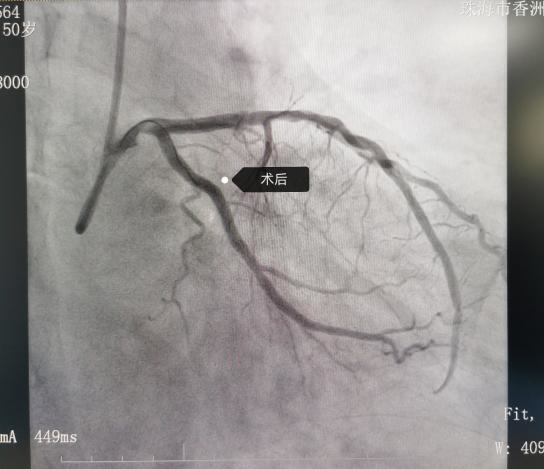

患者王某某,因反复胸闷1年余,加重2天入院。冠脉造影示:右优势型冠脉,左主干无狭窄,前降支近中段弥漫性狭窄30%~50%,第一对角支开口狭窄70%,回旋支近中段狭窄90%伴轻度钙化,右冠中段狭窄20%,各支TIMI血流均为3级。

为了精准介入治疗,心血管代谢医学科李绍波介入团队在IVUS指导下行冠脉支架植入术。IVUS示回旋支近中段轻度钙化,最窄处MLA1.86mm²,斑块负荷78%。于该处植入2.75×25mm药物洗脱支架一枚,高压球囊扩张后复查IVUS示支架膨胀及贴壁良好,无撕裂夹层,MLA增至6.05mm²。手术成功进行,患者症状缓解,已顺利出院。